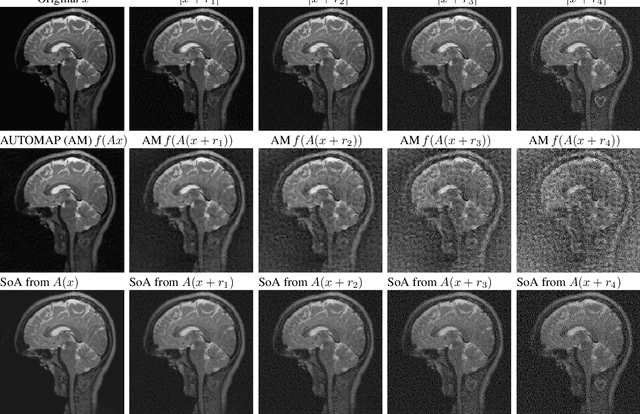

Abstract:There is overwhelming empirical evidence that Deep Learning (DL) leads to unstable methods in applications ranging from image classification and computer vision to voice recognition and automated diagnosis in medicine. Recently, a similar instability phenomenon has been discovered when DL is used to solve certain problems in computational science, namely, inverse problems in imaging. In this paper we present a comprehensive mathematical analysis explaining the many facets of the instability phenomenon in DL for inverse problems. Our main results not only explain why this phenomenon occurs, they also shed light as to why finding a cure for instabilities is so difficult in practice. Additionally, these theorems show that instabilities are typically not rare events - rather, they can occur even when the measurements are subject to completely random noise - and consequently how easy it can be to destablise certain trained neural networks. We also examine the delicate balance between reconstruction performance and stability, and in particular, how DL methods may outperform state-of-the-art sparse regularization methods, but at the cost of instability. Finally, we demonstrate a counterintuitive phenomenon: training a neural network may generically not yield an optimal reconstruction method for an inverse problem.

Abstract:Deep learning, due to its unprecedented success in tasks such as image classification, has emerged as a new tool in image reconstruction with potential to change the field. In this paper we demonstrate a crucial phenomenon: deep learning typically yields unstablemethods for image reconstruction. The instabilities usually occur in several forms: (1) tiny, almost undetectable perturbations, both in the image and sampling domain, may result in severe artefacts in the reconstruction, (2) a small structural change, for example a tumour, may not be captured in the reconstructed image and (3) (a counterintuitive type of instability) more samples may yield poorer performance. Our new stability test with algorithms and easy to use software detects the instability phenomena. The test is aimed at researchers to test their networks for instabilities and for government agencies, such as the Food and Drug Administration (FDA), to secure safe use of deep learning methods.